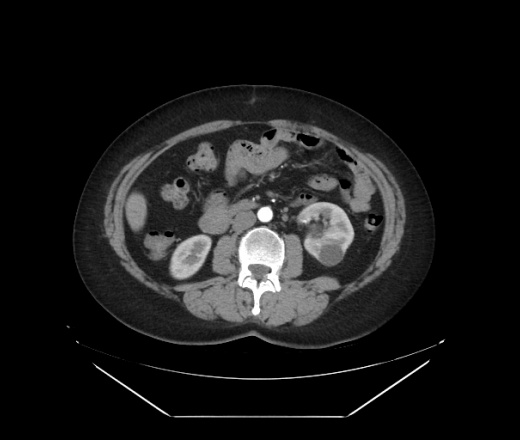

Женщина направлена по поводу кист левой почки, подготовка к перативному лечению. Случайная находка в правой доле печени: два подкапсульных образования с обызвествлением стенки, и очаг понижения плотности визуализирующийся только в венозную фазу.

...и очаг понижения плотности визуализирующийся только в венозную фазу - гемангиома. ...два подкапсульных образования с обызвествлением стенки - одно мне кажется вообще не в печени а рядом, другое - прогностического значения не имеет - типа кальцинат..